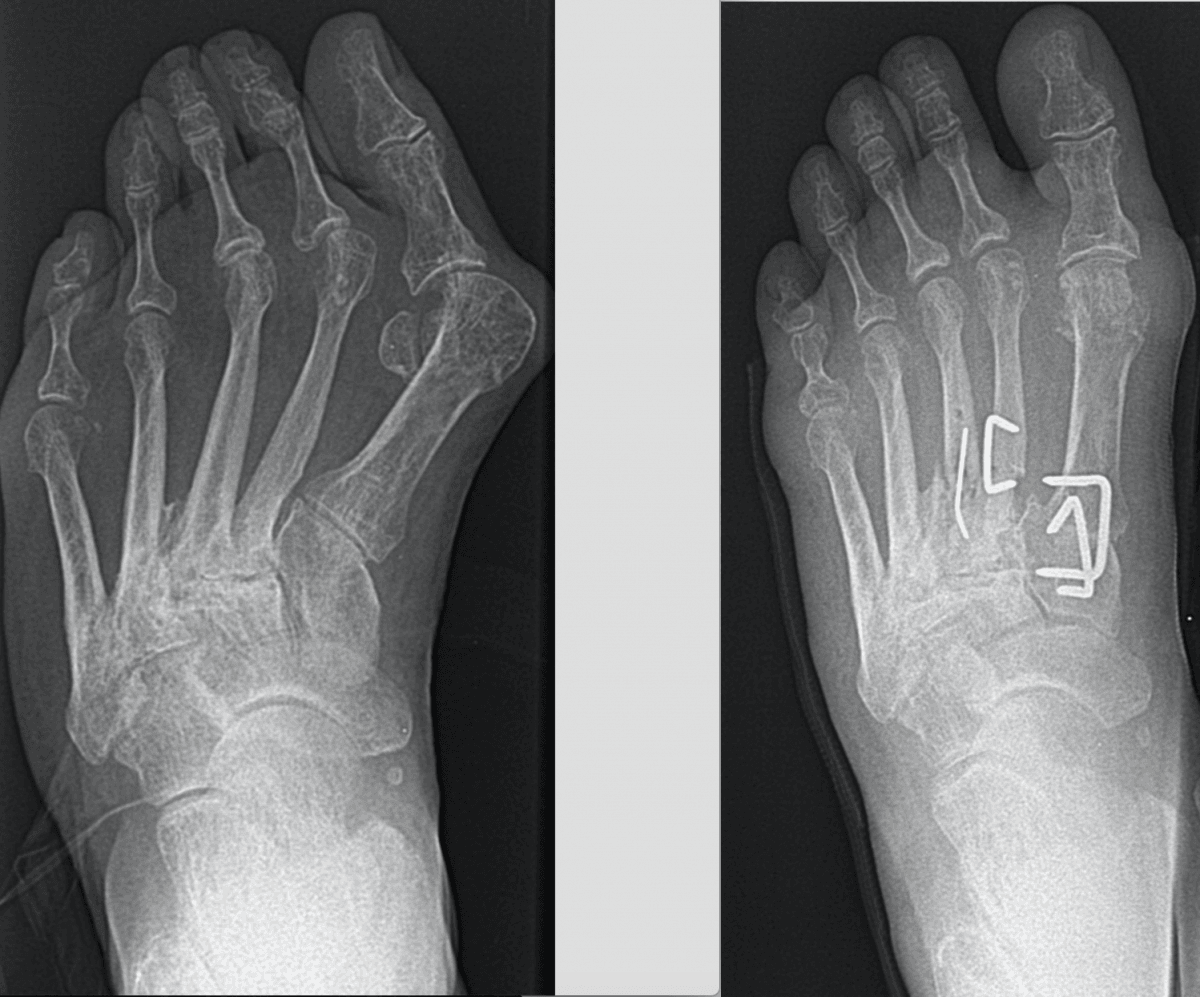

Children’s feet are constantly growing and developing, making it crucial to address any issues early on. Neglecting foot problems in children can lead to long-term complications, affecting their mobility and overall health. Common pediatric foot Hollywood issues include flat feet, heel pain, ingrown toenails, and foot fractures. Addressing these problems promptly with professional care ensures that your child can run, play, and grow without discomfort or hindrance.

At Hollywood Podiatry, we understand the concerns parents have regarding their children’s foot health. Our services are tailored to meet these concerns, providing peace of mind that your child is receiving the best possible care. Early intervention and proper pediatric foot fracture treatment can prevent more serious conditions from developing, ensuring your child’s feet are healthy and strong.